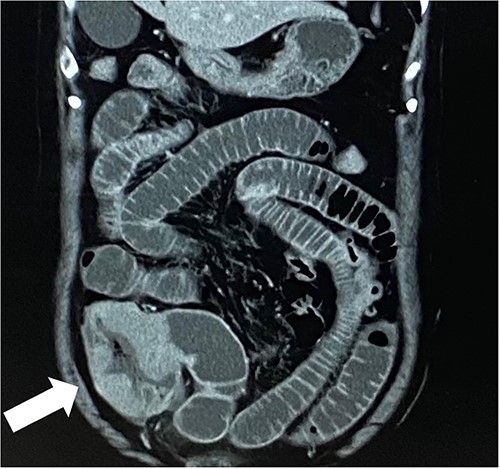

A 79-year-old woman, who had been taking MTX 4.0 mg/week for rheumatoid arthritis since she was 64 years old, came to our hospital complaining of vomiting repeatedly. Physical examination revealed no tenderness in the abdomen, but the abdomen was distended and a mass was observed in the right lower abdomen. Contrast-enhanced computed tomography revealed a mass lesion with contrast effect in the cecum and multiple peritoneal tumors (Figs 1 and 2).